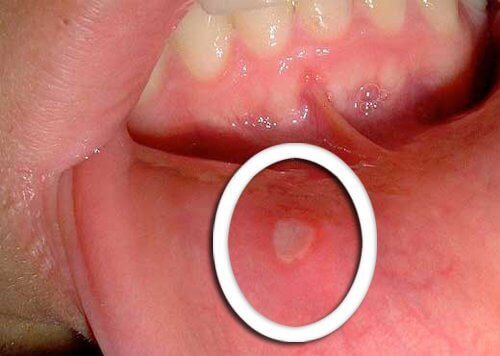

Om zweren en aften te behandelen

Was een stukje avocadoschil en kauw hierop zonder het door te slikken. Laat het vocht dat uit de schil komt de mond rond gaan. Herhaal dit een paar keer achter elkaar en gooi de schil vervolgens weg.